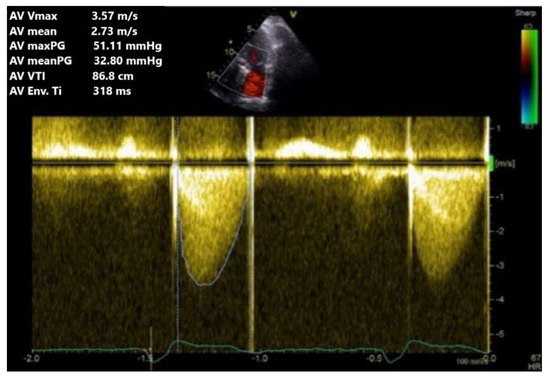

Subsequently, by using apical three- and five-chamber views, continuous Doppler interrogation (CW) of the aortic prosthesis is conducted using a Doppler sample passing as parallel to the colour Doppler flow as possible (Figure 9). Transprosthetic gradients, maximum velocity, acceleration time, ejection time, and velocity time integral (VTI) in LVOT are the aortic prosthesis parameters used as a baseline for aortic mechanical valve evaluation (Table 3).

Figure 9.

TTE CW Doppler. Obstruction of aortic prosthesis with moderate maximum and medium gradients and velocity.

In addition, an increase in the mean gradient by more than 50% compared to the initial value or an increase in the absolute value of the mean gradient by more than 10 mmHg is considered pathological if there is no hyperdynamic status to explain these values [8].

The acceleration time is indexed to the ejection time, due to the dependence on the heart rate. The pathological values for prosthesis obstruction are over 100 ms and for the indexed-to-ejection fraction time, more than 0.37. Both DVI and acceleration time are parameters less dependent on flow and can also be used in the presence of concomitant aortic regurgitation [18].